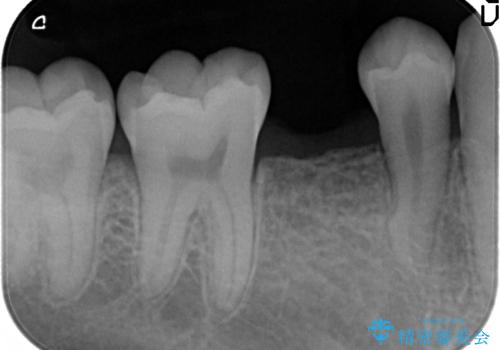

- 当院で矯正治療後、奥歯(前から5番目の歯)のインプラントを行いました。

元々乳歯が残っており、永久歯が欠損していました。

また、一番後ろの永久歯(7番目)の周りに骨がたくさんあり、そこの骨の形を整えて削ってあげたほうが、7番目の歯がしっかり歯茎の炎症も治りやすい状況でした。